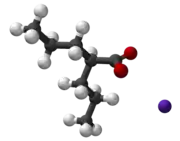

| Other names | Valproic acid; Sodium valproate (sodium); Valproate semisodium (semisodium); 2-Propylvaleric acid |

| Chemical and physical data | |

| Formula | C8H16O2 |

| Molar mass | 144.211 g·mol−1 |

| 3D model (JSmol) | |

Valproate's precise mechanism of action is unclear.[1][5] Proposed mechanisms include affecting GABA levels, blocking voltage-gated sodium channels, and inhibiting histone deacetylases.[6][7] Valproic acid is a branched short-chain fatty acid (SCFA) made from valeric acid.[6]

Valproic acid (VPA) is an organic weak acid. The conjugate base is valproate. The sodium salt of the acid is sodium valproate and a coordination complex of the two is known as valproate semisodium.[14]

Valproic acid is a branched short-chain fatty acid and a derivative of valeric acid.[6]

| Formula | C8H15NaO2 |

| Molar mass | 166.196 g·mol−1 |

| 3D model (JSmol) | |